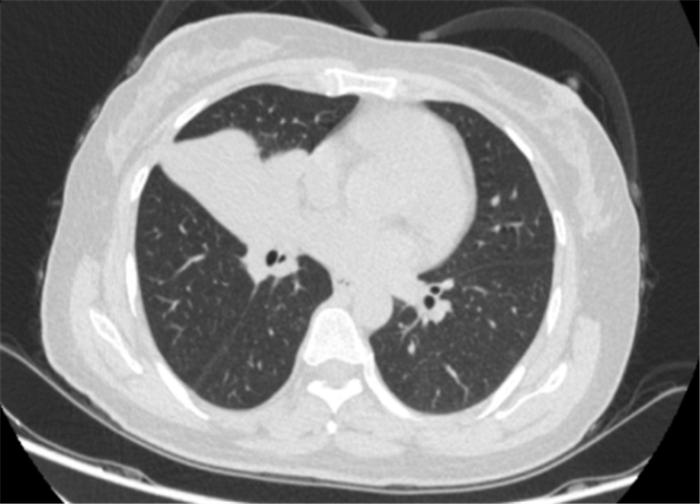

李女士(化名)年近50岁,因为咳嗽、咳痰两个多月到我院就诊。一经检查,发现她患有肺癌(右肺鳞癌并右侧肺门淋巴结转移),已经属于晚期(T3N1M0 IIIA)。

肺癌主要的组织类型是非小细胞肺癌(NSCLC),手术是治疗非小细胞肺癌的重要手段。然而,经过多学科会诊,李女士的病灶靠近心脏,加上手术对患者的身体状况要求也高,无法进行手术治疗。多学科专家反复讨论治疗方案,在和家属多次沟通下,最终选择由呼吸与危重症医学科采用免疫新辅助治疗,实现降期缩瘤再手术治疗。

患者治疗前基线胸部CT